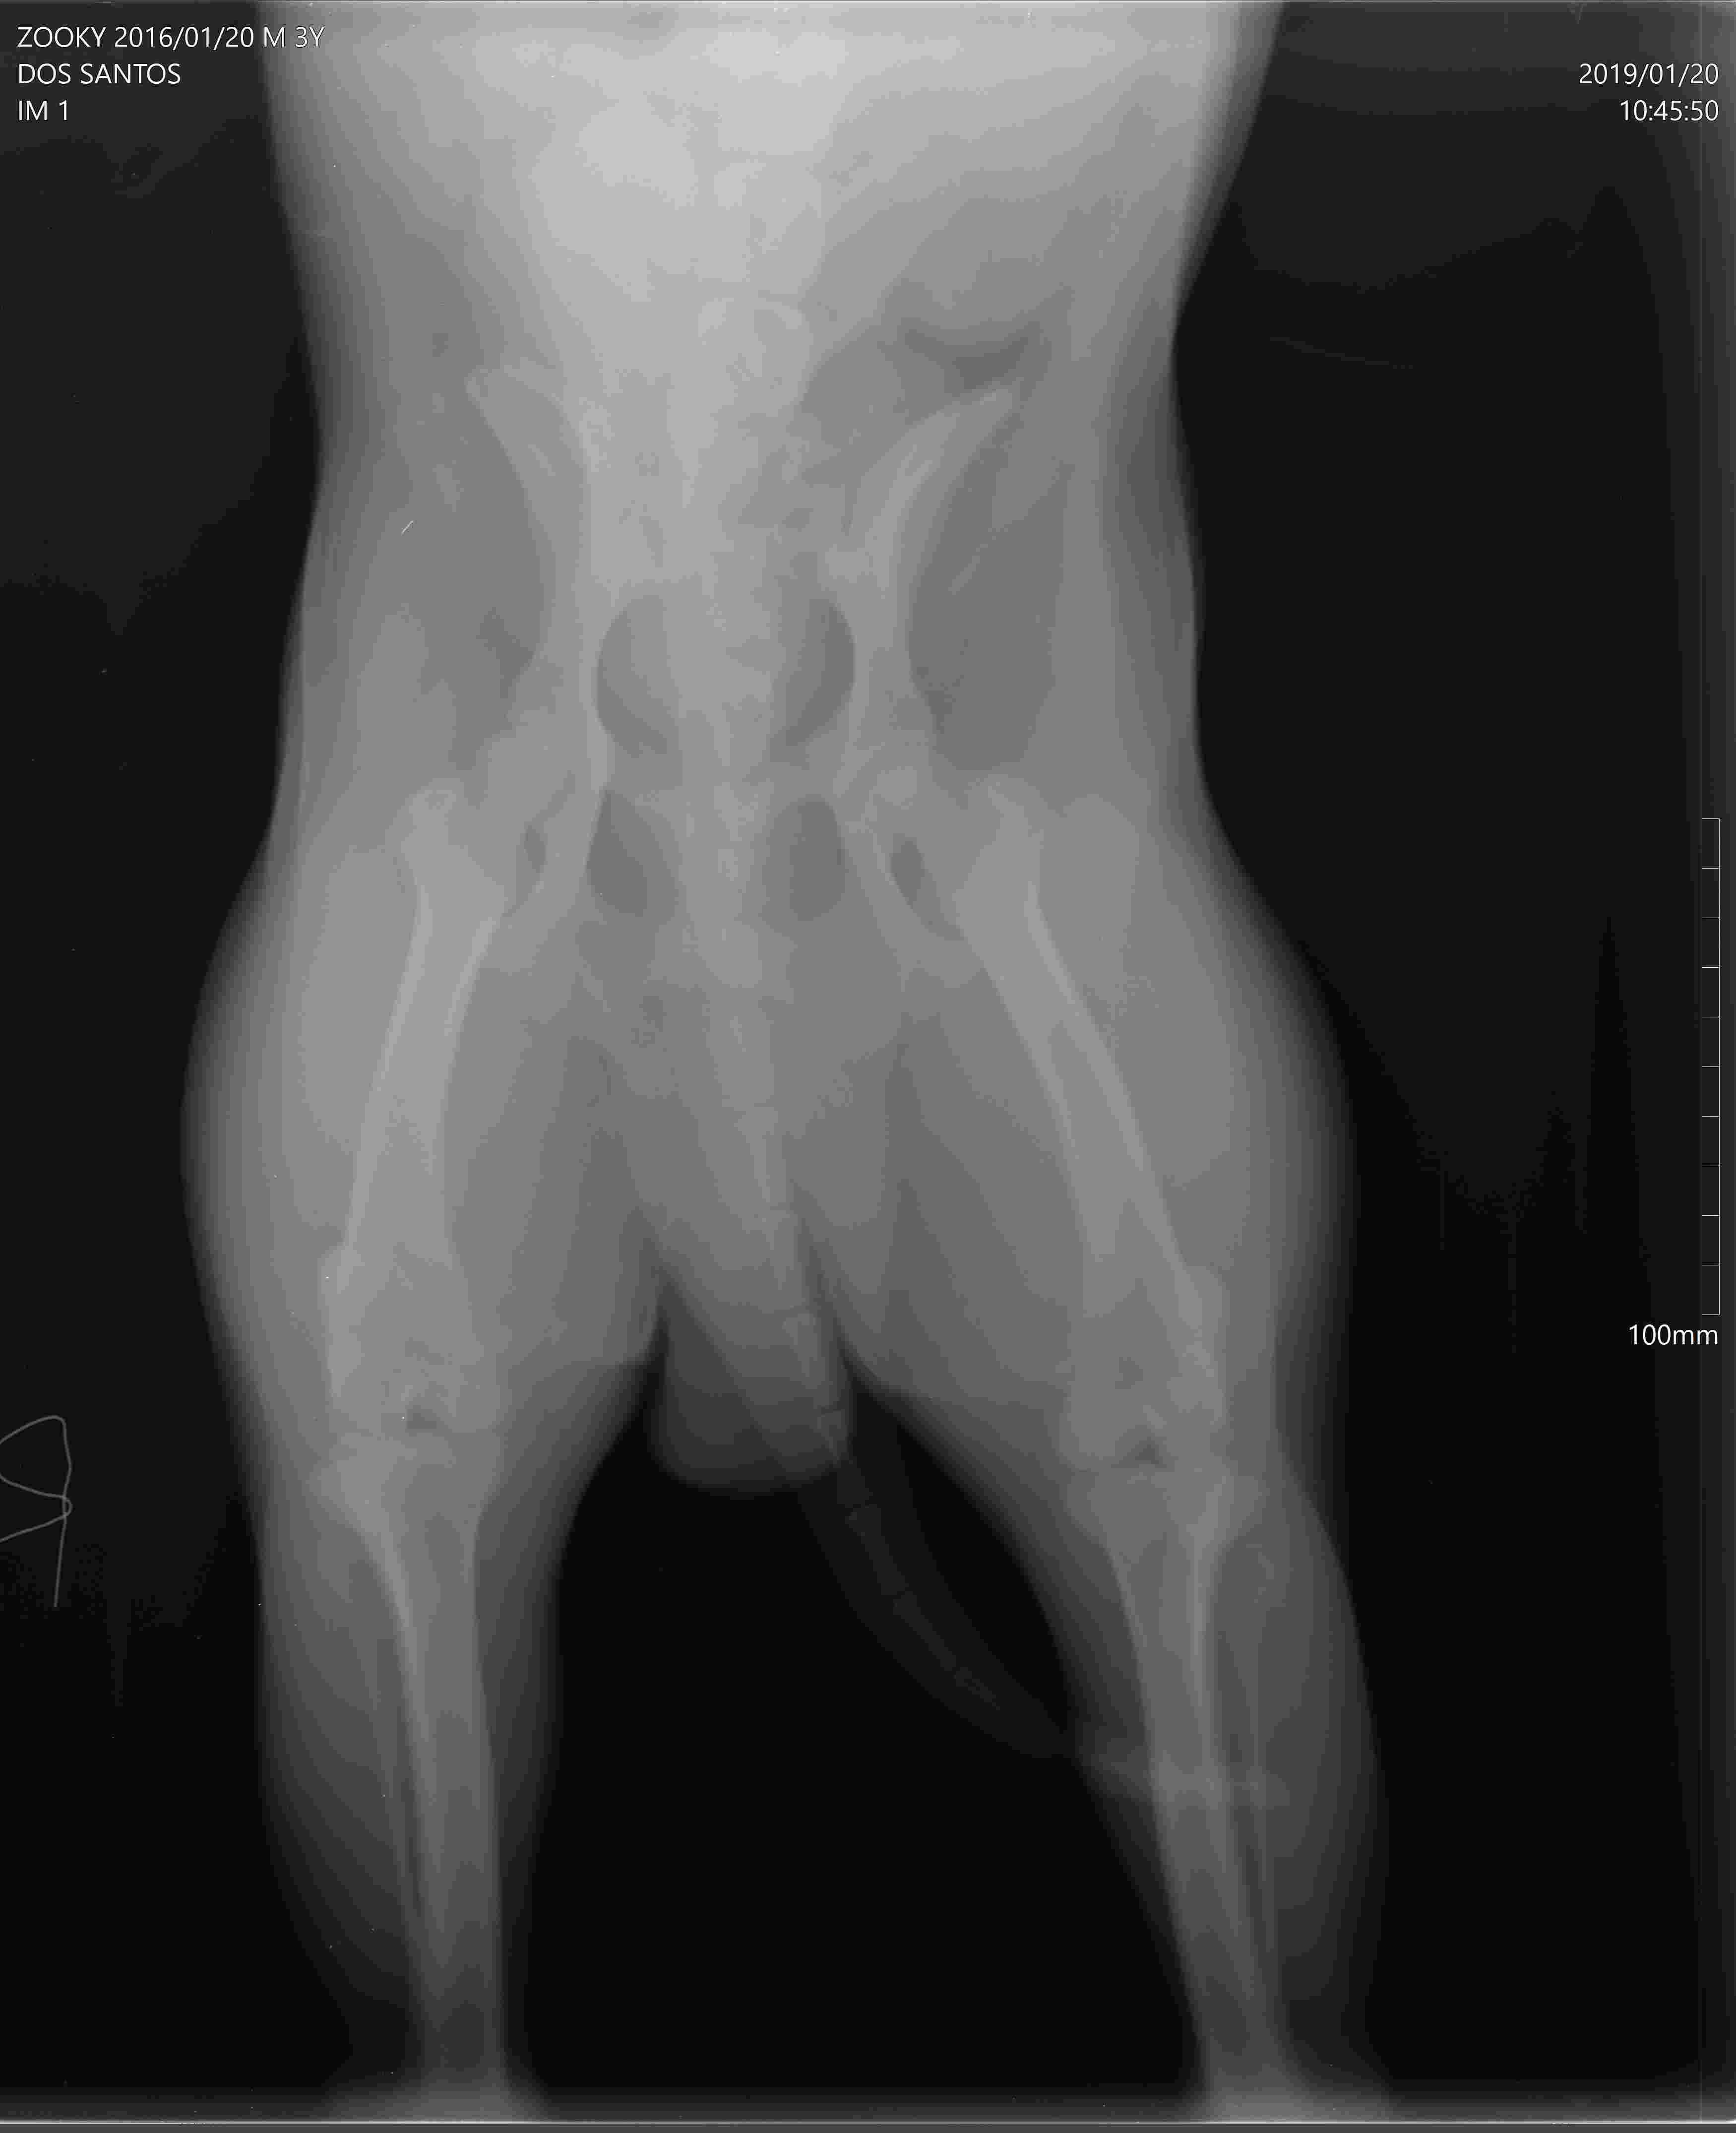

Hi :) My Chow caught up on a leash string and cant step on his right paw after incident . Went to vet immediately ( x-Ray is clear , test ligament is clear ) After two days he can step on his right paw already but still limping . After two weeks all the same and nothing change . Medicine is finished and there is no improvement at all from 2 days after incident . His mood getting worst . Eat just a bit and no movements around the house . Maybe you could advice what else can we do :(Thank you

Poor guy. Unfortunately x-rays aren't clear when posted here. They come out extremely fuzzy. Also they only include the hips and knees, he may have an issue lower down on his leg (paw, metatarsal region). Wherever he seems painful on physical exam is where we tend to focus our x-ray on. You can consider having the x-rays repeated focusing on his lower leg only. I would also consider a consult with an orthopedic specialist. He may even need to have an ultrasound or MRI done to detect the underlying issue for certain. Whenever there are no obvious x-ray findings you are often dealing with a ligament injury which can occur in the knee or even the lower metatarsal region. In the meantime I would continue to cage rest Zooky and give him pain medication as needed to keep him comfortable. I hope that Zooky is able to make a full and speedy recovery soon! Best wishes and take care.